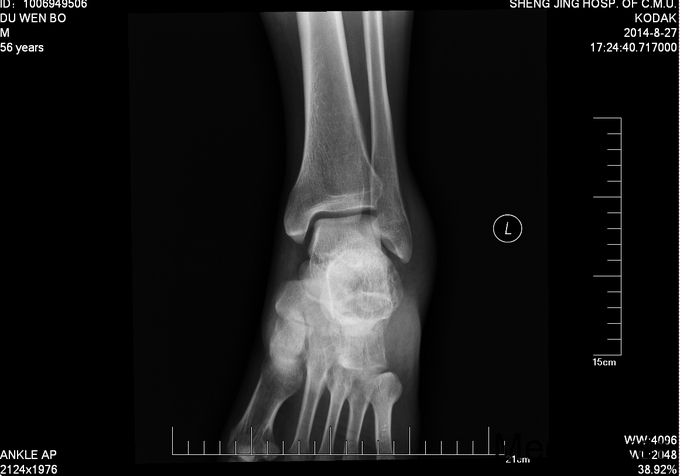

左跟骨骨折sanders2型

患者及其家属自述于2015-10-17 13:30 因在自家干活时不慎从2米高梯子上摔下,当时患者意识清醒,无法站立,左踝部疼痛、肿胀、活动受限,以“左踝部骨折”为诊断收入我科;患者伤来无发热、无头晕、恶心呕吐,无呼吸困难,既往饮食睡眠可,大小便正常; 左踝部肿胀明显,压痛阳性,左踝部活动受限,可闻及骨擦音及骨擦感;患肢皮肤感觉较健侧无明显异常,足趾可活动,足背动脉可触及;